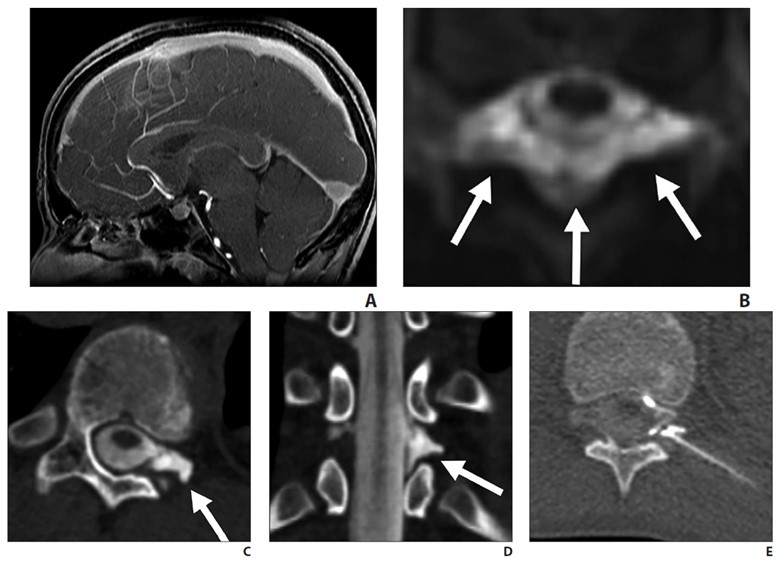

Fig. 3—14-year-old boy with sudden-onset orthostatic headache after playing golf.

A, Sagittal contrast-enhanced T1-weighted MR image shows sagging of brainstem, dural venous sinus, and pituitary engorgement.

B, Axial reconstruction of 3D T2-weighted fat-saturated MR image of spine shows epidural fluid collection confined to dorsal and lateral epidural spaces at T10 level (arrows) without ventral component.

C and D, Axial (C) and coronal (D) slices through left lateral decubitus dynamic CT myelography show pooling of contrast material along lateral epidural space at T10–11 (arrows), arising from ruptured T10 nerve root sleeve.

E, Intraprocedural CT image obtained during CT-guided epidural fibrin glue patching shows percutaneous epidural injection of fibrin and autologous blood. Treatment provided only temporary relief, so patient underwent primary surgical repair.